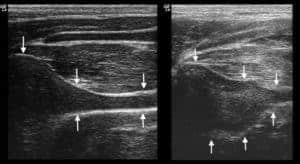

Ultrasound for Arytenoid Chondritis Diagnosis?

Ultrasonography could be a valuable adjunct tool for diagnosing equine arytenoid chondritis.